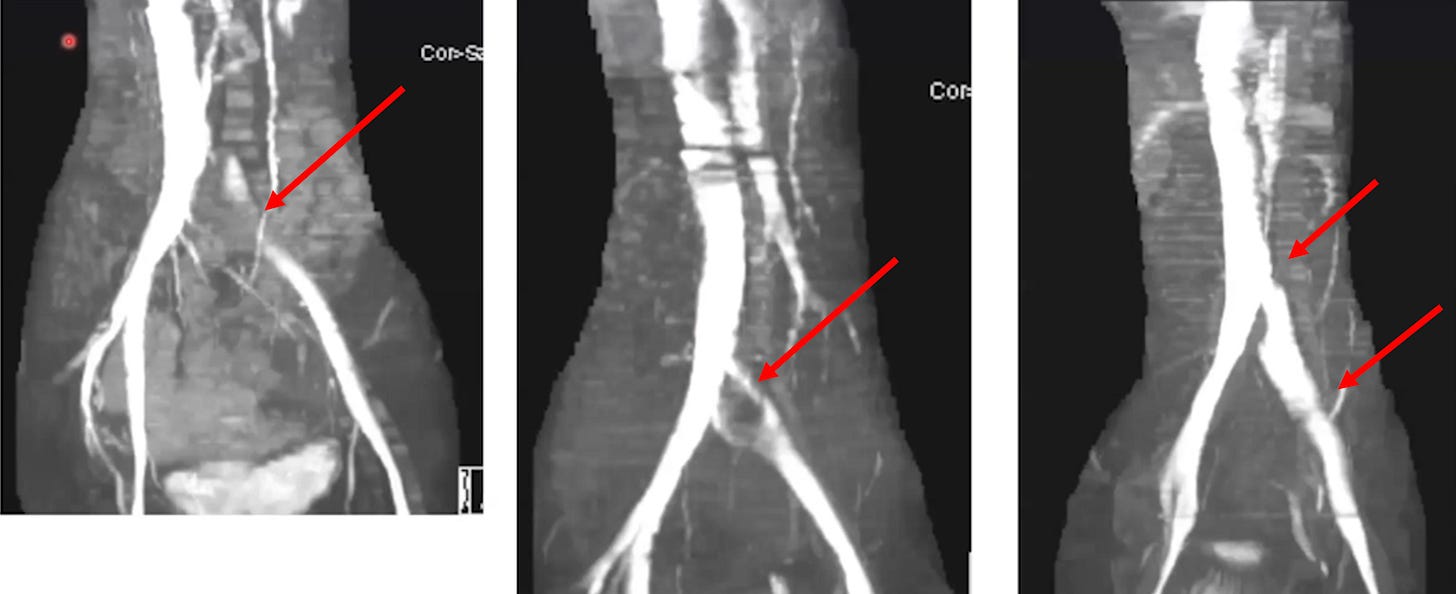

•A condition known as May-Thurner syndrome affects slightly over 20% of the population. In it, the (high pressure) right common iliac artery overlies and compresses the (low pressure) left common iliac vein against the lumbar spine

Normally, individuals with this syndrome do not notice it, but in some cases it can predispose them to unexpected blood clots (due to venous return being obstructed).

•Dr. Vaughan believes that the (well-documented) damage the spike protein causes to walls of the blood vessels weakens the iliac vein enough that pressure from the iliac artery can cause it to collapse. In turn, he has collected compelling radiography to prove it.

•If an iliac vein compression is treated with anticoagulation, this typically improves the symptoms of it, but once the anticoagulants are stopped, the symptoms return (as the source of the clotting has not been addressed). For this reason, iliac vein compressions are often treated with stenting, which some patients (but not all) have reported significant benefit from.